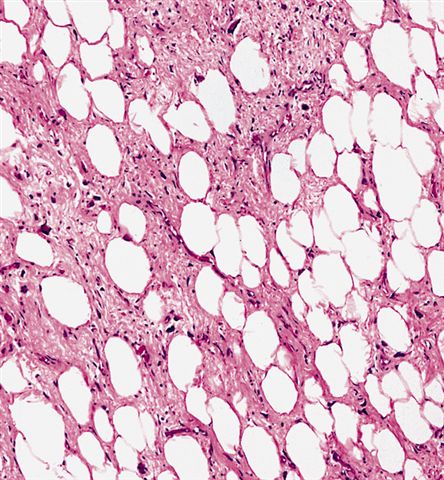

Contributed by Michael Clay, M.D., Melanie Bourgeau, M.D. and AFIP

Morphologic variability:

- Lipoma-like subtype

- Most common subtype

- Scattered atypical cells may be diffuse or exceedingly rare

- Frequently contains lipoblasts

- Grossly, can be indistinguishable from lipoma

- Depends on subtype, generally composed of mature fat with variably sized adipocytes and bands of fibrotic stroma containing spindle cells with enlarged, hyperchromatic nuclei

- Can be markedly atypical

- Cellularity is low and mitotic figures are uncommon

- Atypical cells are more commonly found in fibrous septa and in a perivascular distribution